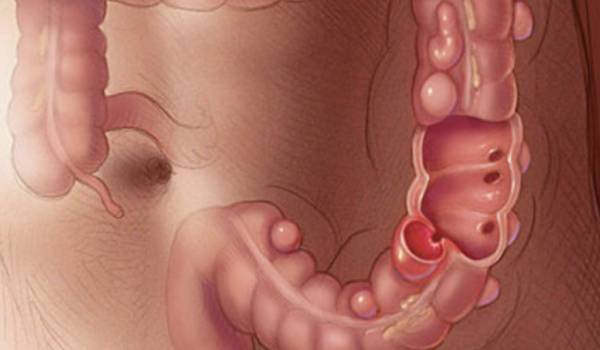

Es la presencia de pequeñas hernias en forma de saco en la pared del intestino grueso.

Instrumento médico que permite la identificación de Enfermedades de Colon proximal y distal así como el recto.